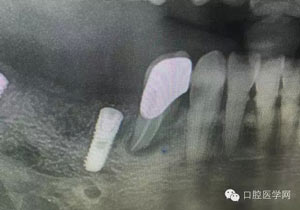

病例1:患者迫切希望保留自己的這一顆牙齒,根尖周陰影比較大,二度松動.而且旁邊有種植修復(fù)體,和患者溝通好后,治療好后觀察一個月后冠修復(fù),因為有種植的后期修復(fù),所以有了機會觀察,術(shù)后三個月和術(shù)后四個月,根尖恢復(fù)的還算不錯,希望能夠繼續(xù)觀察下去.這樣子的病例,做的時候我們一定要非常的小心,和患者要有充分的溝通以及不同科室的溝通然后決定怎么樣做比較好,假如就是出現(xiàn)了問題,到時候我們也比較好處理些,免得我們自己到時候不好收場。